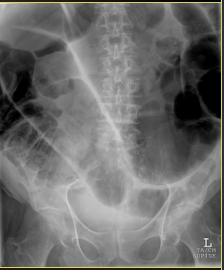

What does this show?

distended small bowel loops

bowel wall b/w loops is thickened and edematous (large white arrow)

No air is seen in the colon or rectum